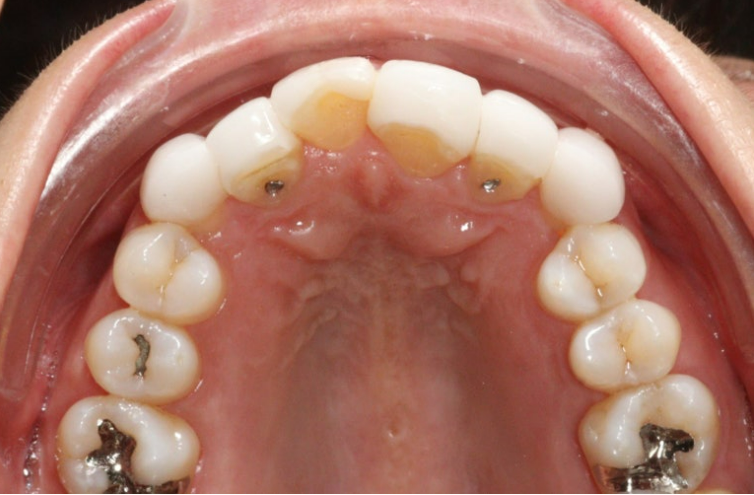

24.05

3개월에 걸쳐 앞니 교정을 간단하게 하고 6월 드디어 무삭제 라미네이트 치료를 했습니다.

24.06

무삭제 라미네이트의 실제 두께를 알 수 있는 사진입니다.

삭제를 하지 않았음에도 원래 치아보다 두꺼워짐이 거의 없죠

무삭제 라미네이트의 핵심은 바로 얇게 만드는 것 입니다.